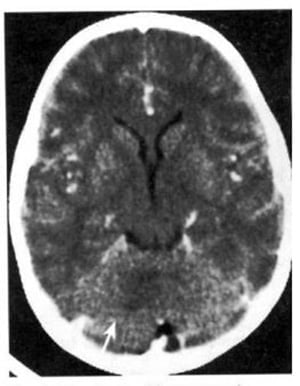

1.4. U màng ống nội tủy (Hình 1.59)

Dấu hiệu XQCLĐT:

– Khối u không đồng nhất trong não thất 4; 50% chứa những đám calci. Bắt chất cản quang đồng nhất hoặc không.

– Thường gặp não úng thủy.

Chú giải:

– Rất thường trước 10 tuổi. Có khuynh hướng xuất huyết.

– U dưới màng ống nội tủy là một biến thể xảy ra ở người già hơn. Chúng chứa tế bào màng ống nội tủy và tế bào đệm.

Hình 1.59. U màng ống nội tủy. Trước tiêm (a), không đồng nhất nằm ở vùng não thất 4 (mũi tên). Sau tiêm (b), bắt chất cản quang mạnh và không đồng nhất.